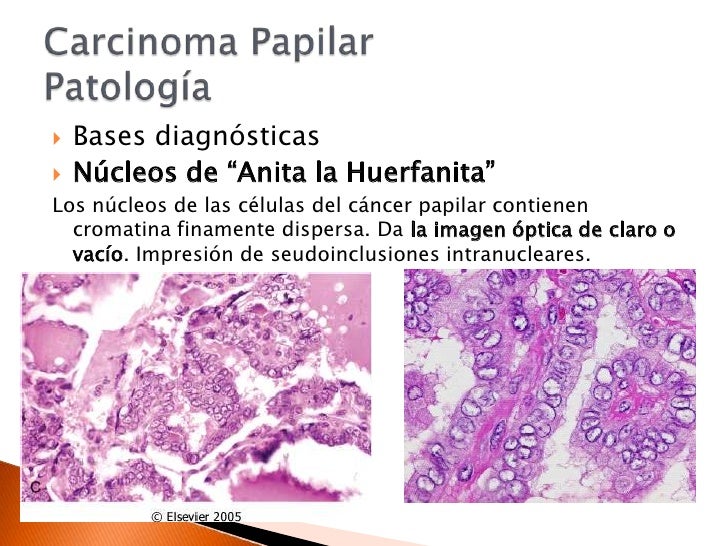

Carcinoma papilar de tiroides

V Congreso Virtual Hispanoamericano de Anatomía Patológica CARCINOMA